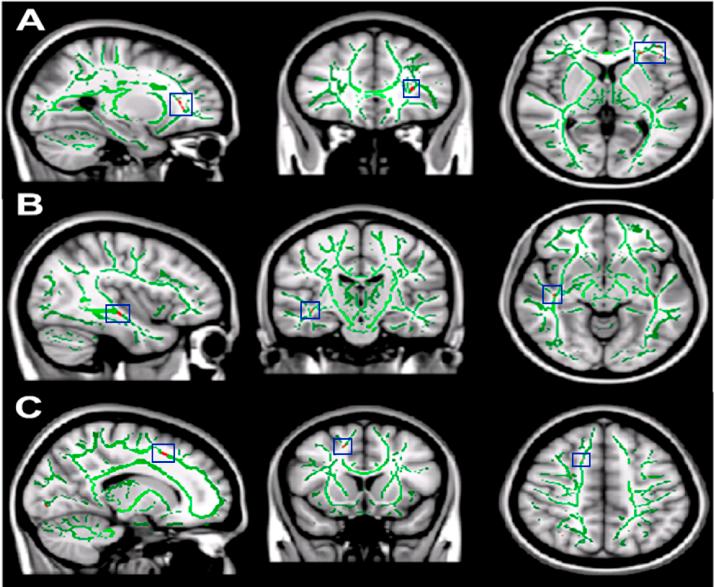

Self-imposed short sleep durations are increasingly commonplace in society, and have considerable health and performance implications for individuals. Reduced sleep duration over multiple nights has similar behavioural effects to those observed following acute total sleep deprivation, suggesting that lack of sleep affects brain function cumulatively. A link between habitual sleep patterns and functional connectivity has previously been observed, and the effect of sleep duration on the brain's intrinsic functional architecture may provide a link between sleep status and cognition. However, it is currently not known whether differences in habitual sleep patterns across individuals are related to changes in the brain's white matter, which underlies structural connectivity. In the present study we use diffusion-weighted imaging and a group comparison application of tract based spatial statistics (TBSS) to investigate changes to fractional anisotropy (FA) and mean diffusivity (MD) in relation to sleep duration and quality, hypothesising that white matter metrics would be positively associated with sleep duration and quality. Diffusion weighted imaging data was acquired from a final cohort of 33 (23-29 years, 10 female, mean 25.4 years) participants. Sleep patterns were assessed for a 14 day period using wrist actigraphs and sleep diaries, and subjective sleep quality with the Pittsburgh Sleep Quality Index (PSQI). Median splits based on total sleep time and PSQI were used to create groups of shorter/longer and poorer/better sleepers, whose imaging data was compared using TBSS followed by post-hoc correlation analysis in regions identified as significantly different between the groups There were significant positive correlations between sleep duration and FA in the left orbito-frontal region and the right superior corona radiata, and significant negative correlations between sleep duration and MD in right orbito-frontal white matter and the right inferior longitudinal fasciculus. Improved sleep quality was positively correlated with FA in left caudate nucleus, white matter tracts to the left orbito-frontal region, the left anterior cingulum bundle and the white matter tracts associated with the right operculum and insula, and negatively correlated with MD in left orbito-frontal white matter and the left anterior cingulum bundle. Our findings suggest that reduced cumulative total sleep time (cTST) and poorer subjective sleep quality are associated with subtle white matter micro-architectural changes. The regions we identified as being related to habitual sleep patterns were restricted to the frontal and temporal lobes, and the functions they support are consistent with those which have previously been demonstrated as being affected by short sleep durations (e.g., attention, cognitive control, memory). Examining how inter-individual differences in brain structure are related to habitual sleep patterns could help to shed light on the mechanisms by which sleep habits are associated with brain function, behaviour and cognition, as well as potentially the networks and systems responsible for variations in sleep patterns themselves.

自我设定的短睡眠时间在社会中越来越普遍,对个人的健康和表现有相当大的影响。多个晚上睡眠时长减少所产生的行为影响,与急性完全睡眠剥夺后观察到的影响相似,这表明睡眠不足会累积影响大脑功能。此前已观察到习惯性睡眠模式与功能连接之间存在联系,而睡眠时间对大脑内在功能结构的影响可能为睡眠状态与认知之间提供一种联系。然而,目前尚不清楚个体之间习惯性睡眠模式的差异是否与大脑白质的变化有关,而白质是结构连接的基础。在本研究中,我们使用扩散加权成像和基于束的空间统计学(TBSS)的组间比较应用,来研究分数各向异性(FA)和平均扩散率(MD)与睡眠时间和质量相关的变化,假设白质指标与睡眠时间和质量呈正相关。扩散加权成像数据是从33名(年龄在23 - 29岁之间,10名女性,平均25.4岁)参与者的最终队列中获取的。使用腕部活动记录仪和睡眠日记对睡眠模式进行了为期14天的评估,并使用匹兹堡睡眠质量指数(PSQI)评估主观睡眠质量。基于总睡眠时间和PSQI的中位数分割用于创建短/长睡眠者和差/好睡眠者组,对他们的成像数据使用TBSS进行比较,随后在组间差异显著的区域进行事后相关分析。睡眠时间与左侧眶额区域和右侧放射冠上部的FA之间存在显著正相关,而睡眠时间与右侧眶额白质和右侧下纵束的MD之间存在显著负相关。睡眠质量改善与左侧尾状核、连接至左侧眶额区域的白质束、左侧前扣带回束以及与右侧岛盖和脑岛相关的白质束中的FA呈正相关,与左侧眶额白质和左侧前扣带回束中的MD呈负相关。我们的研究结果表明,累积总睡眠时间(cTST)减少和主观睡眠质量较差与白质微观结构的细微变化有关。我们确定的与习惯性睡眠模式相关的区域局限于额叶和颞叶,它们所支持的功能与先前已证明受短睡眠时间影响的功能(如注意力、认知控制、记忆)一致。研究大脑结构的个体差异如何与习惯性睡眠模式相关,有助于阐明睡眠习惯与大脑功能、行为和认知相关的机制,以及潜在地揭示负责睡眠模式变化的网络和系统。